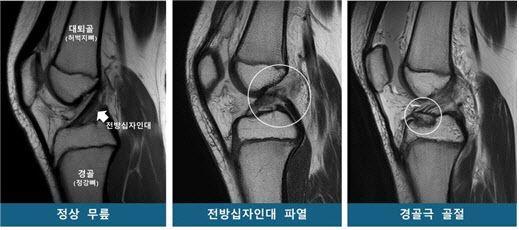

[이데일리 이순용 기자] 운동 중 무릎을 다친 소아청소년 중 일부는 십자인대가 끊어지고, 일부는 무릎뼈가 골절된다. 이런 차이가 ‘타고난 무릎 모양’ 때문에 발생한다는 연구 결과가 나왔다. 대퇴과간 절흔 폭(무릎뼈 사이 공간)이 좁으면 전방십자인대 파열 위험이 높아지고, 경골(정강뼈) 바깥쪽 관절면의 가파른 경사는 전방십자인대 파열과 경골극 골절 모두에 영향을 미친다는 사실이 규명됐다. 이 결과는 무릎 부상 위험이 높은 소아청소년을 선별하고, 개인별 맞춤 치료 지침을 마련하는 근거가 될 것으로 기대된다.

연구팀은 소아청소년을 53명씩 ▲전방십자인대 파열군 ▲경골극 골절군 ▲대조군(정상 무릎)으로 구분하고 연령·성별을 매칭했다. 이후 MRI를 재구성한 3차원 영상을 바탕으로 14개의 해부학적 지표를 분석했다.

그 결과, 두 무릎 손상군은 대조군보다 ‘경골 바깥쪽 관절면 경사’가 유의미하게 높았다. 통계 분석에 따르면 경사가 높을수록 전방십자인대 파열 및 경골극 골절 발생 위험이 각각 1.42배, 1.33배 증가해, 이 값이 소아청소년의 주요 무릎 손상에 대한 위험인자로 확인됐다. 반면, ‘대퇴과간 절흔 폭(무릎뼈 사이 공간)’은 전방십자인대 파열군에서만 유의미한 연관성이 있었다. 특히 이 폭이 넓을수록 파열 위험이 감소하는 보호 효과가 확인됐다.

연구팀은 경골 바깥쪽 관절면의 경사가 가파를수록 무릎에 무게가 실릴 때 대퇴골(허벅지뼈)이 바깥쪽으로 회전하며, 그 결과 전방십자인대가 과부하되어 파열이나 경골극 골절로 이어질 수 있다고 설명했다. 또한 대퇴과간 절흔 폭이 넓을 경우, 전방십자인대가 대퇴골과 덜 충돌하기 때문에 파열 위험이 낮아지는 경향이 있다고 밝혔다.